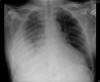

TC exostosis occipital congénica.

TC exostosis occipital congénita.